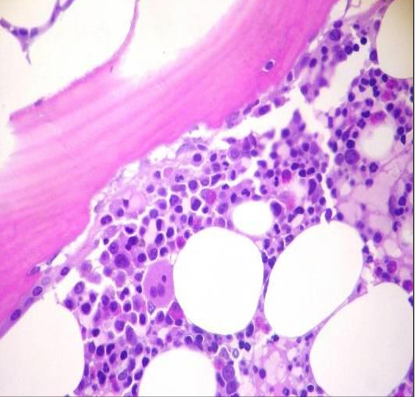

MÉDULA ÓSEA

Biopsia médula ósea

Valoración cantidad tejido hematopoyético/tejido adiposo

BIOPSIA MÉDULA OSEA Y ASPIRADO MEDULAR